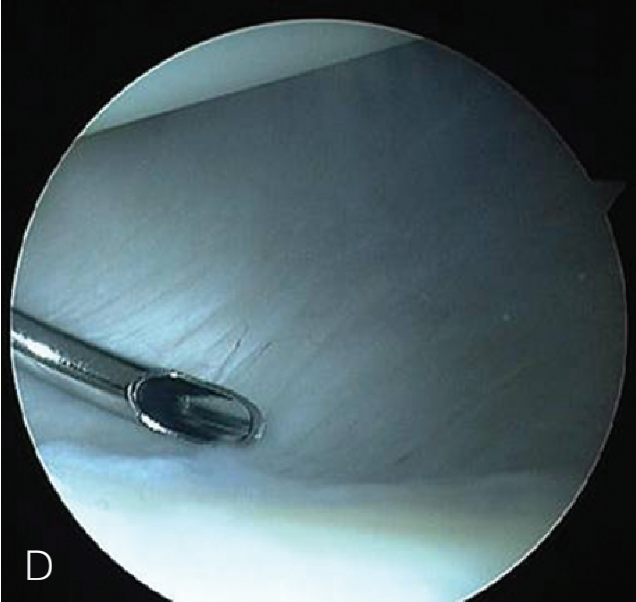

修复处准备

肩袖部分撕裂的修复